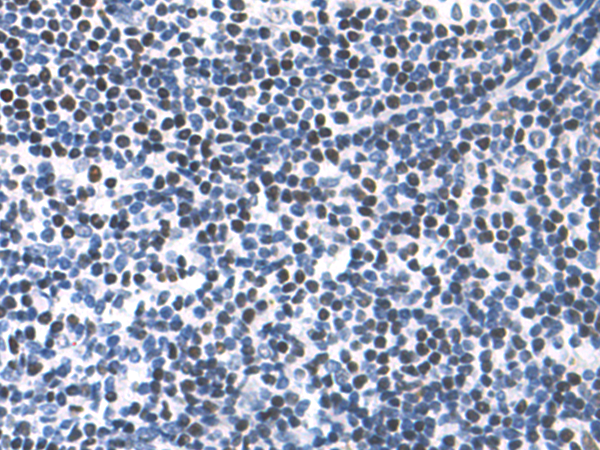

分类: 科研抗体货号: P06958别名: BGR, BRGL, PRTDNY3, PRTD-NY3应用: IHC反应种属: Human